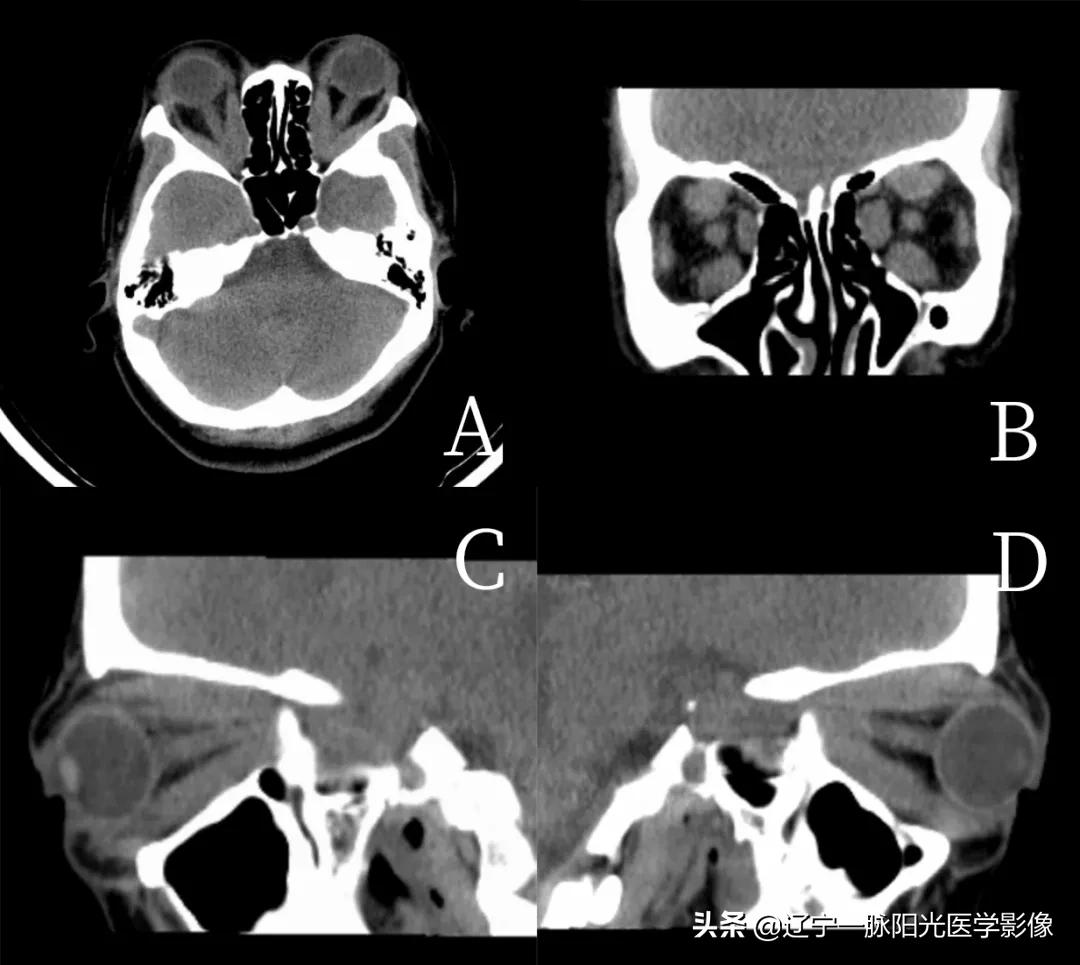

简要病史:女,24 岁,右侧眼部胀痛 10 天,加重 3 天。

影像所见:

图 A 平扫轴位示右侧内直肌增粗,形成类圆形软组织影,大小约为 1.3×0.7 cm,平扫呈低密度,CT 值约 45 HU

图 B、C、D 增强轴位、冠状位、矢状位示病灶中度强化,CT 值约 53 HU,眼球未见明显受压移位,泪腺结构未见明显异常,骨质结构未见明显破坏

最终病理诊断为肌炎型炎性假瘤